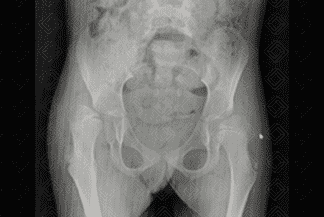

Texto alternativo para a imagem Figuras 4 e 5. Créditos: Dra. Elazir Mota - Rio de Janeiro/RJ

Descrição das imagens: Radiografia de quadril AP e Lowenstein (posição da rã). Paciente infantil neuropata. Observa-se luxação superior e lateral dos quadris bilateralmente. A medida mais usada nas radiografias é a linha de Shenton.

2. Radiografia de quadril: E xame realizado nos lactentes mais velhos, após 4-6 meses, momento no qual a epífise femoral inicia sua ossificação (neste contexto não há mais janela acústica para realização do ultrassom de quadril). Algumas linhas devem ser analisadas:

• Linha de Hilgenreiner : Uma linha horizontal traçada através do topo das áreas claras da cartilagem trirradiada;

• Linha de Perkins: É uma linha vertical perpendicular à linha de Hilgenreiner que tangencia a margem acetabular lateral. Estas duas linhas dividem o quadril em quatro quadrantes, devendo a cabeça femoral estar situada nos quadrantes inferior e medial;

• Linha (arco) de Shenton: É uma linha traçada entre a borda medial do colo femoral e a borda superior do forame obturador. Ela deve ter um contorno contínuo.